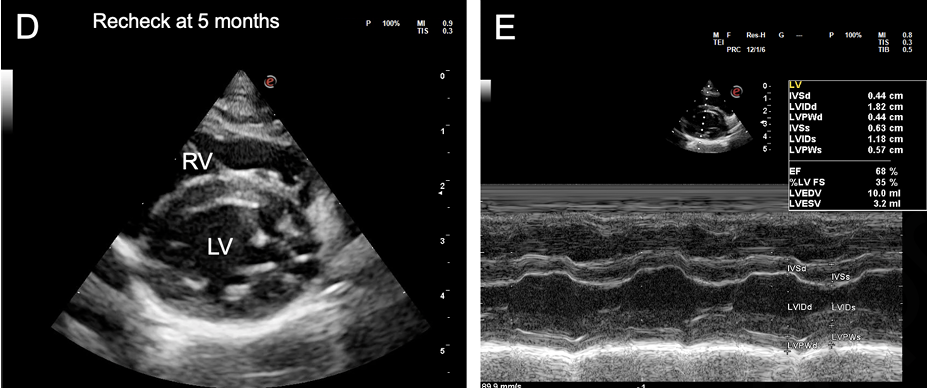

- 치료 후 심장 기능의 회복: 심부전 치료와 항생제 치료를 시작한 후, 2.5개월, 5개월, 9개월 차에 진행된 추적 심장 초음파 검사에서 놀라운 변화가 관찰되었습니다. 확장되었던 심방과 심실의 크기가 정상 범위로 줄어들고, 저하되었던 심실 수축 기능 또한 정상으로 회복되는 '역 리모델링(reverse remodeling)'이 명확하게 확인되었습니다.

- 약물 치료 중단: 5개월 차 추적 검사 후 이뇨제와 항혈전제를 중단하였고, 9개월 차에는 심장 기능이 안정적으로 유지됨에 따라 강심제인 피모벤단까지 모두 중단할 수 있었습니다. 모든 심장 약물을 중단한 후에도 고양이는 임상 증상 없이 양호한 상태를 유지했습니다.